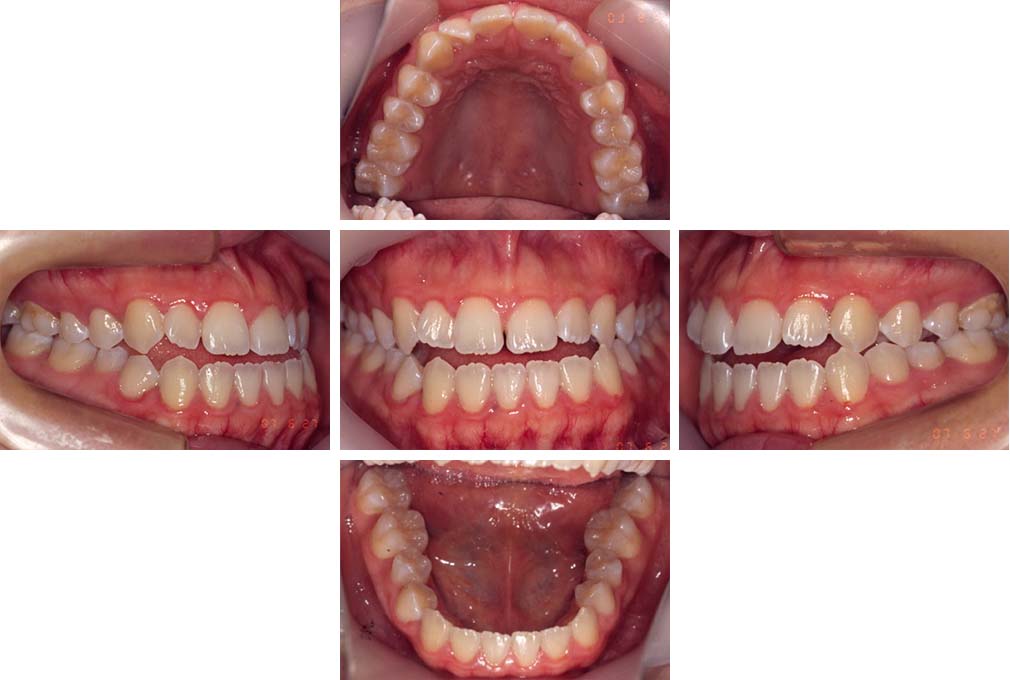

CASE:03

上下顎前突

初診時年齢 18歳4か月

性別 男性

治療費の目安 105万円程度(治療開始時)

歯列の乱れは著しくなく上顎右側側切歯が捻転し口蓋側へ転位していた。また、問診の中で患者さんから最も重視する治療結果として口元の突出の改善の申出があった。下顎が後退した上顎前突傾向ではあったが著しいものではなかった。上下顎前突と診断し上下顎小臼歯抜歯を行っていただき、上下顎舌側マルチブラケット装置を使用して、矯正用アンカースクリューを併用して動的治療を行った。上下顎前歯の後退を十分行い口元の突出感も改善した。治療後10年1か月の来院時には口元の突出感が再発することもなく、下顎前歯の少しの唇舌的なずれはあったが歯列は安定していた。動的治療期間2年2ヵ月間。

治療前

18歳4ヵ月

治療後

動的治療期間2年2カ月間

20歳10か月

10年経過

動的治療終了後10年1カ月

30歳11か月